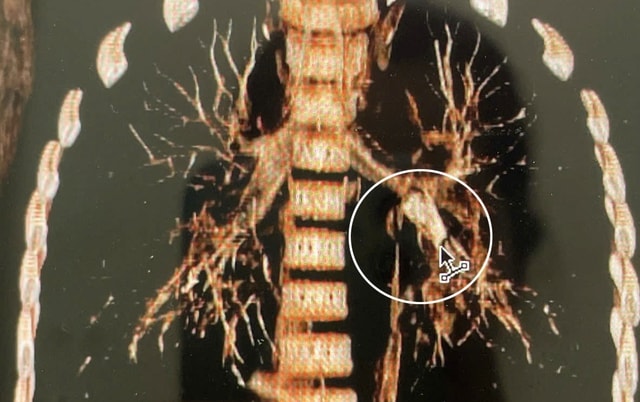

Qua thăm khám lâm sàng, các bác sĩ nghi ngờ trẻ bị hóc dị vật đường hô hấp, nhiều khả năng là đầu ngòi bút. Bệnh nhi được chỉ định chụp CT ngực, kết quả ghi nhận dị vật dạng hình ống, bề dày thành khoảng 1,8mm, chiều dài khoảng 18mm, nằm tại phế quản thùy dưới bên trái, gây cản trở thông khí.

Sau khi hội chẩn chuyên khoa, các bác sĩ quyết định tiến hành nội soi phế quản cấp cứu để lấy dị vật. Thủ thuật được thực hiện an toàn, dị vật là đầu ngòi bút được lấy ra hoàn toàn, không ghi nhận biến chứng trong và sau can thiệp. Sau thủ thuật, tình trạng hô hấp của trẻ cải thiện rõ rệt và tiếp tục được theo dõi, điều trị tại bệnh viện.